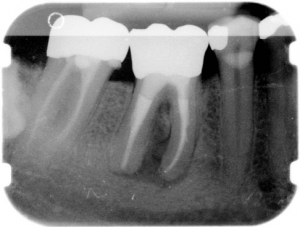

Die Wurzelkanal-Füllung ist notwendig, um Bakterien keinen Raum für eine erneute Ausbreitung zu bieten. Wir verarbeiten die Guttapercha ausschließlich thermoplastisch, also in einem recht aufwendigen Verfahren, bei dem das Material durch Wärme fließfähig gemacht und dann in die Hohlräume verpresst wird. So entsteht die bestmögliche Versiegelung der Hohlräume. Die Aufbereitungstiefe und das Behandlungsergebnis werden mittels Röntgenbildern kontrolliert und dokumentiert.